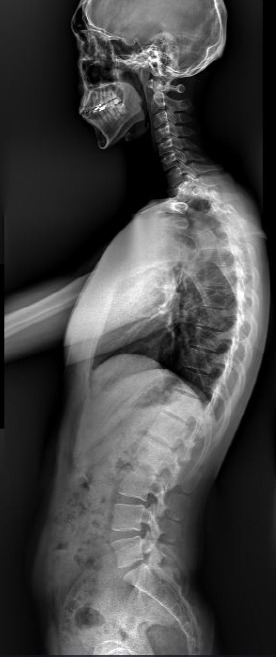

거북목을 가진 사람들은 보통 굽은 등을 함께 갖고 있기 때문에 경추에서 흉추, 요추, 골반까지 생리적인 커브에서 많이 무너져있고 견갑대의 위치가 불안정합니다. 엑스레이로 본다면 위와 형태를 갖고 있는 경우가 대부분입니다. 몸의 무게 중심이 이처럼 앞쪽으로 이동해 있고 경추의 커브가 무너지면서 흉추의 과후만되고 요추는 과전만되는 상태로 생리적인 커브가 무너지는 것입니다.

거북목은 얼굴이 앞으로 나오면서 목의 정상 커브인 c자 커브가 사라지면서 일자커브나 역커브의 형태로 변하고 어깨는 말리고 등은 굽는 특징적인 자세 패턴을 의미합니다.이처럼 일자목, 전방두부자세, 굽은 등과 연관된 거북목은 잘못된 자세 습관에 발생하는 대표적인 질병입니다.